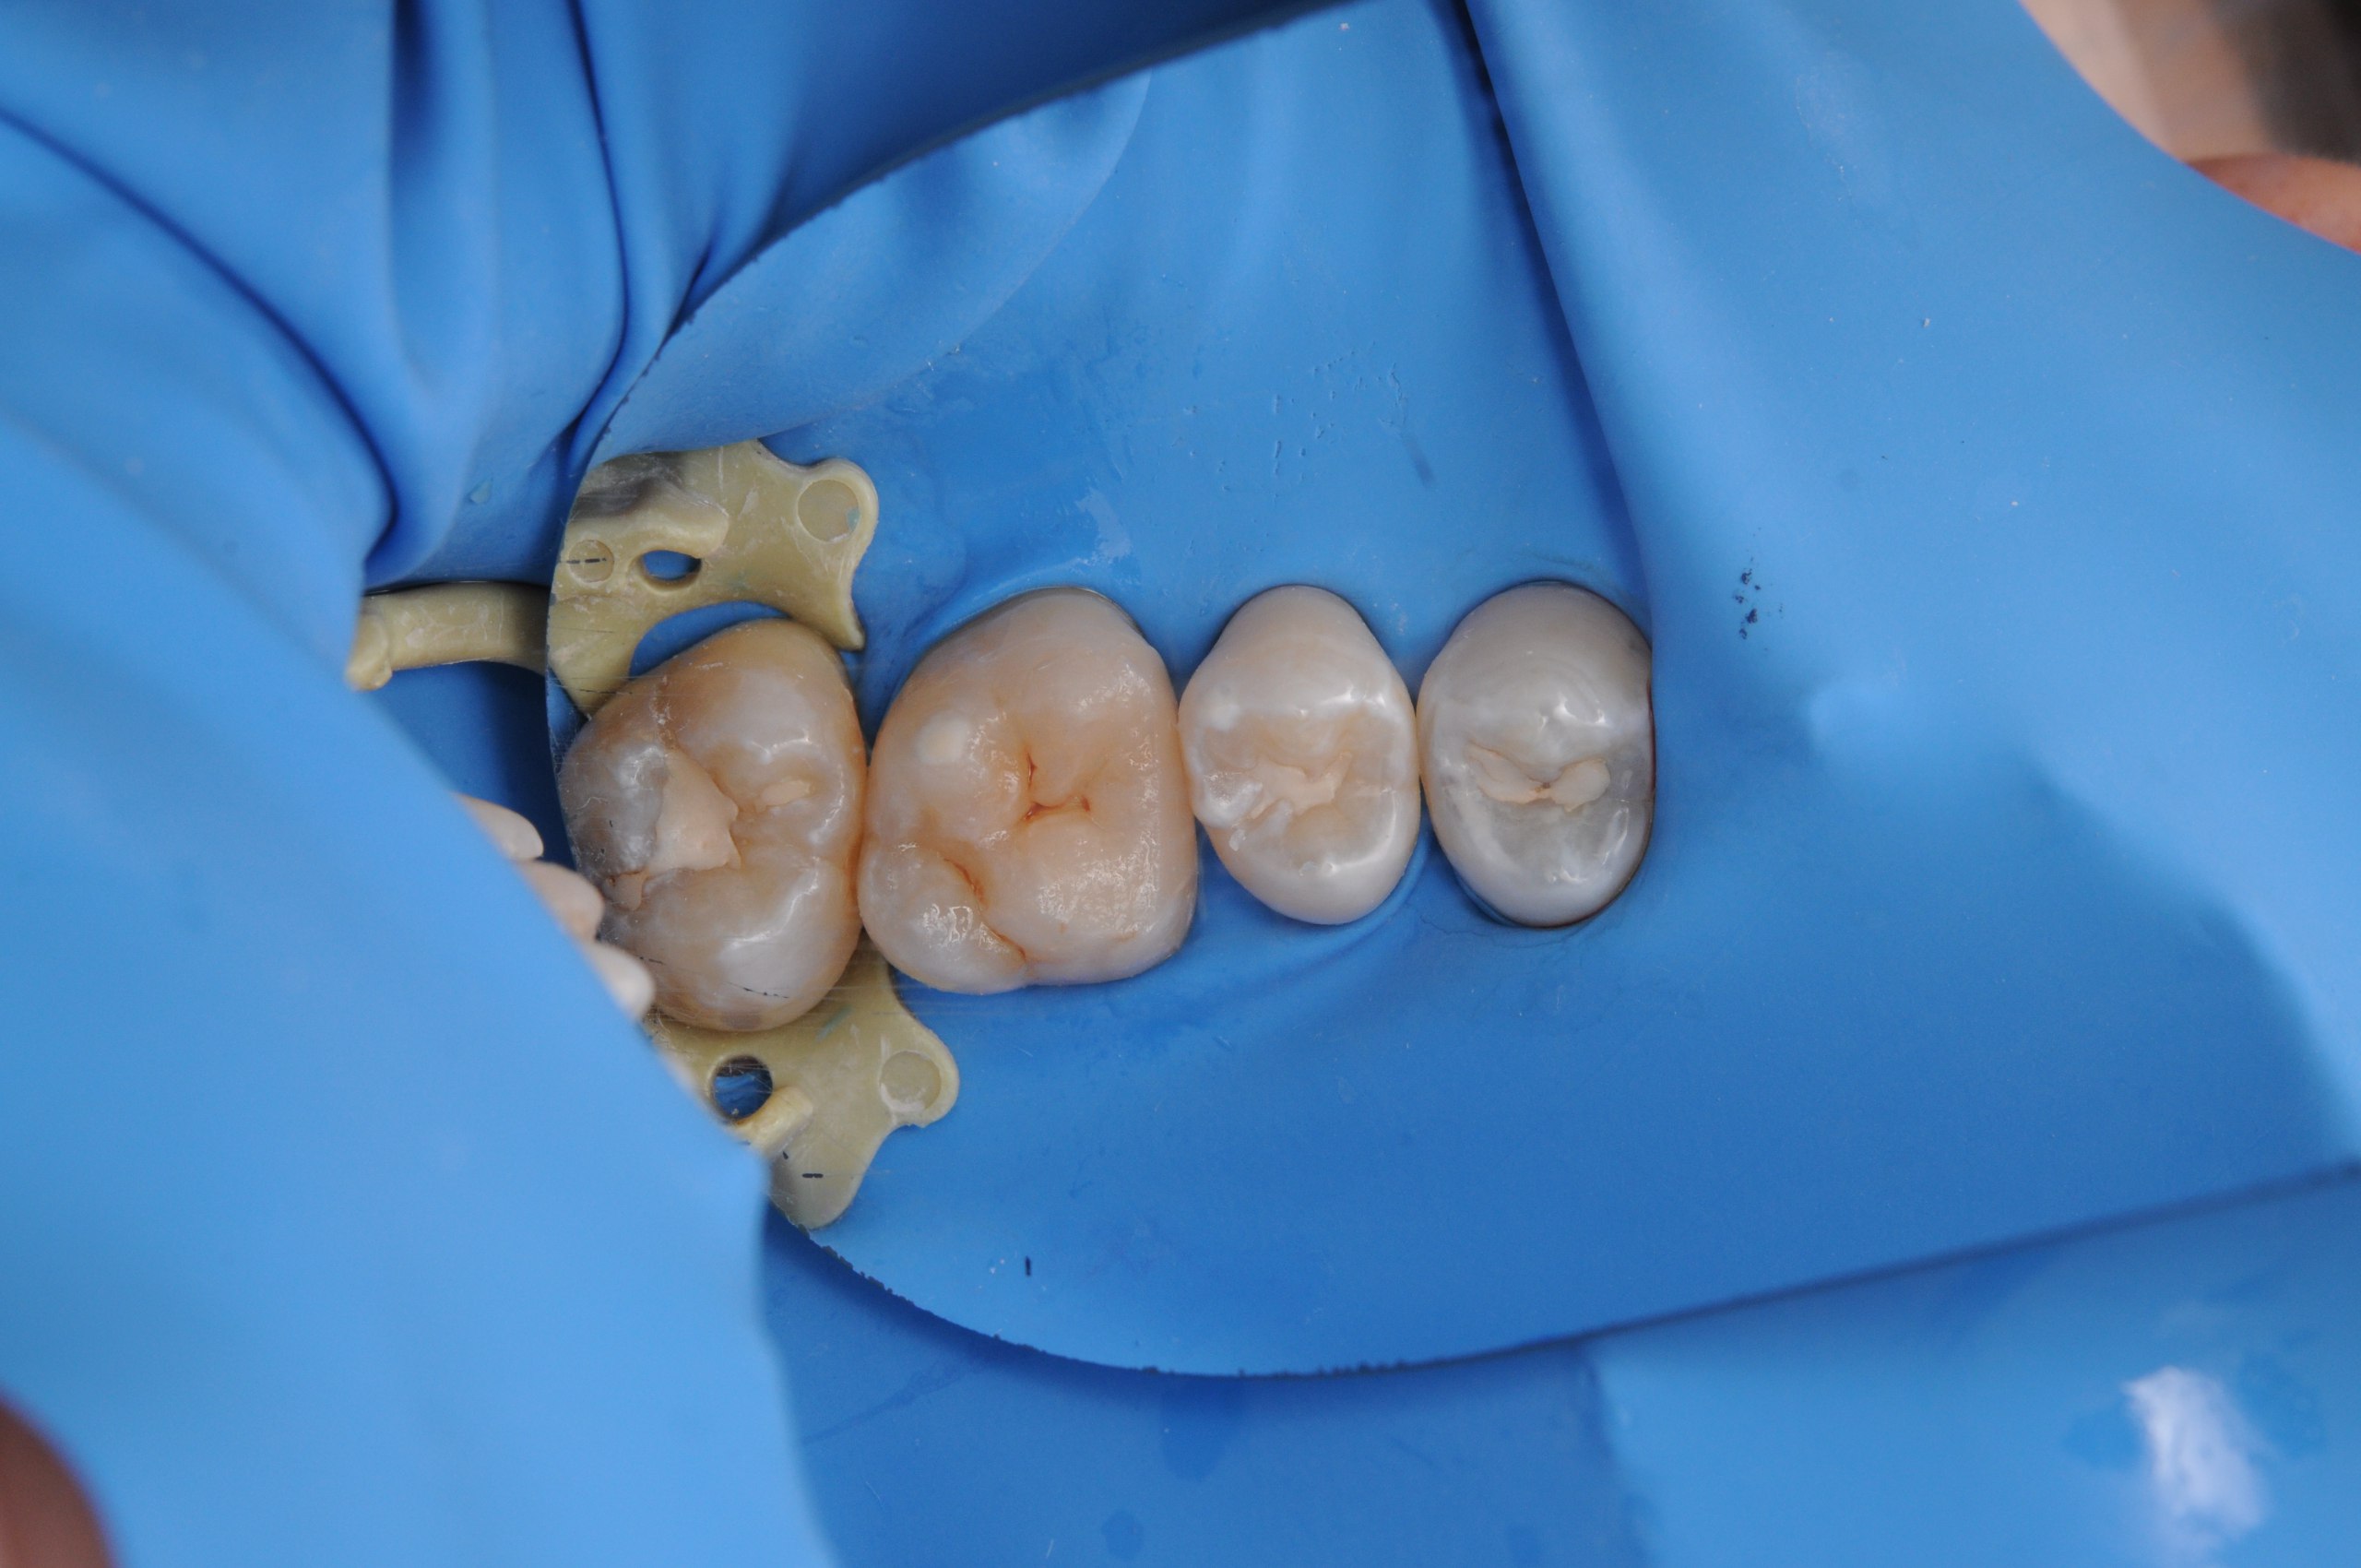

Pacient přišel se starými amalgámovými plombami, které projevovaly známky opotřebení a zbarvení. Navzdory jejich odolnosti mohou tyto plomby časem degradovat a vést k potenciálním komplikacím, jako je kaz nebo prasknutí. K vyřešení tohoto problému byly staré amalgámové plomby pečlivě odstraněny a zuby byly připraveny pro kompozitní plomby. Nové plomby nejen obnovují vzhled zubů, ale také poskytují zlepšenou odolnost. V další návštěvě jsme provedli výměnu dalších starých plomb, které pacient měl, k zachování jeho ústního zdraví a estetiky. Tento případ ukazuje důležitost pravidelných zubních kontrol a včasné výměny starých plomb pro udržení ústního zdraví a estetiky.

1. Před

2. V průběhu

3. V průběhu

4. V průběhu

5. V průběhu

6. Po